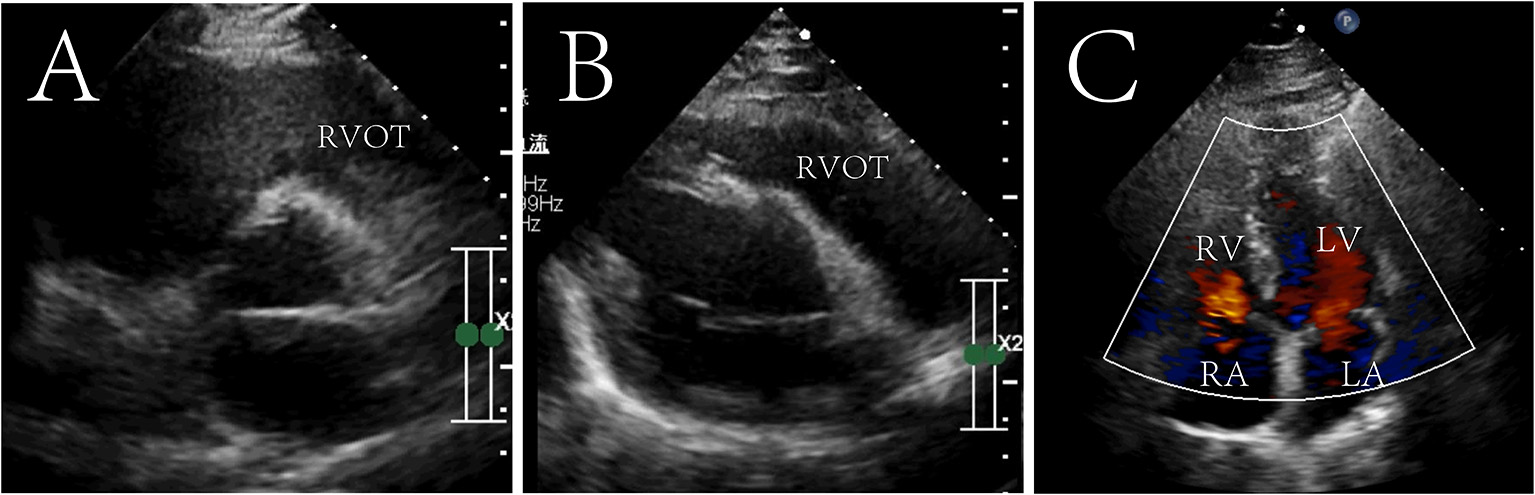

The patient recovered without palpitations and other complications and was discharged on the 6th post-operative day with a recommendation for follow-up. After 7 years of follow-up, no tumor recurrence was found on echocardiography (Figure 3 and Supplementary materials). The diameter of the right atrium decreased from 50 to 35 mm, the right ventricle from 46 to 34 mm, the RVOT from 31 to 25 mm, and the PG across the pulmonary valve to 4 mmHg. The tricuspid valve functioned normally, and no regurgitation was seen.

FIGURE 3

www.frontiersin.org

Figure 3. Seven-year postoperative echocardiography in transthoracic aortic short-axis views (A), right ventricular outflow tract view (B) and four chamber cross section view (C). The tumor did not recur and the right ventricular outflow tract was not obstructed. Right ventricular outflow tract, RVOT; RV, right ventricle; LV, left ventricle; RA, right atrium; LA, left atrium.